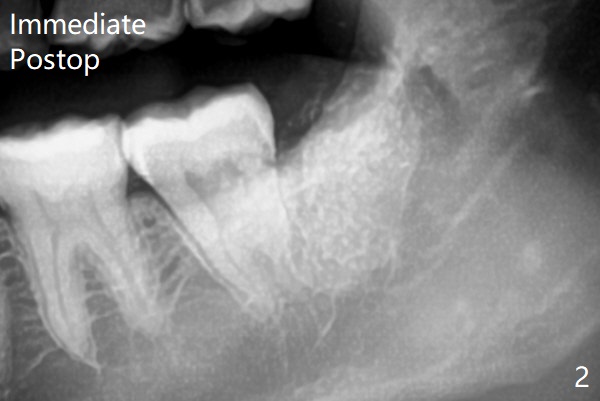

7和8之间只有一层骨皮质(图一:>),8拔除后(图一’),7远中骨质可能退缩,所以植骨尤其重要。医用石膏(Bond Apatite,图二),表面放置1/2胶原塞,4-0 PGA缝合。